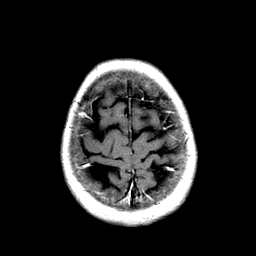

Metastatic Adenocarcinoma of the Colon: T1-weighted MR -- Slice #21

[Home][Help][Clinical] Slice 21